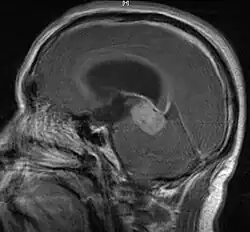

• Mainly located in midline structures, suprasellar region or pineal gland, also basal ganglia and hypothalamus

Location